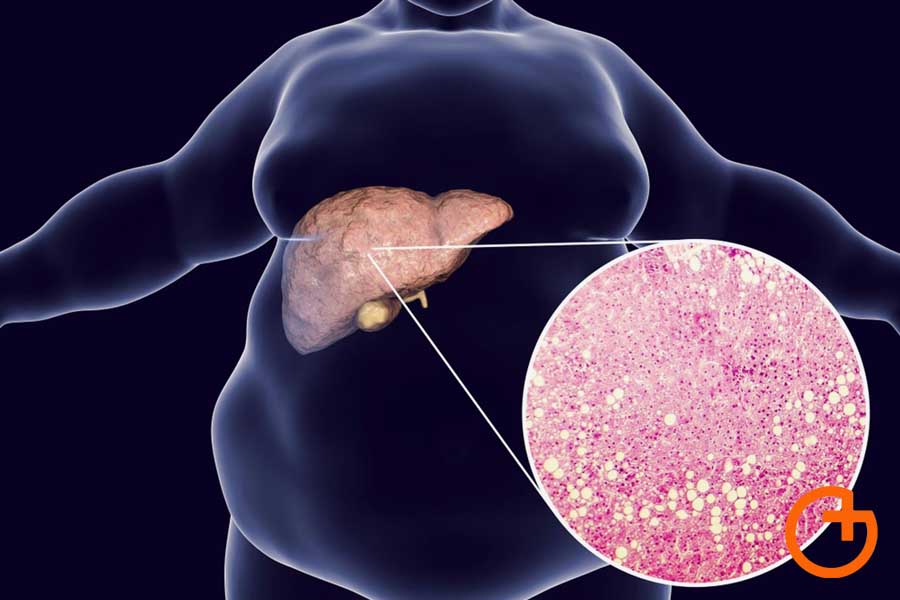

Hígado graso: una enfermedad silenciosa pero reversible

“El hígado graso es la acumulación de grasa en los hepatocitos, las células normales del hígado. Esa grasa genera inflamación crónica y puede progresar a fibrosis y cirrosis. Lo grave es que muchas veces no da síntomas y no se le da la importancia que realmente tiene”, explicó la médica.

La doctora remarcó que se trata de una enfermedad vinculada a la obesidad, la diabetes tipo 2, la hipertensión y el sedentarismo, aunque también puede presentarse en pacientes delgados con resistencia a la insulina. Incluso, advirtió que empieza a detectarse en niños y adolescentes con sobrepeso.

En cuanto al diagnóstico, los estudios más habituales son la ecografía y el hepatograma, que permiten detectar alteraciones en el hígado. “No debemos pensar que sólo afecta a personas con obesidad. También en pacientes delgados o diabéticos tipo 1 podemos encontrar hígado graso”, señaló Nallim.